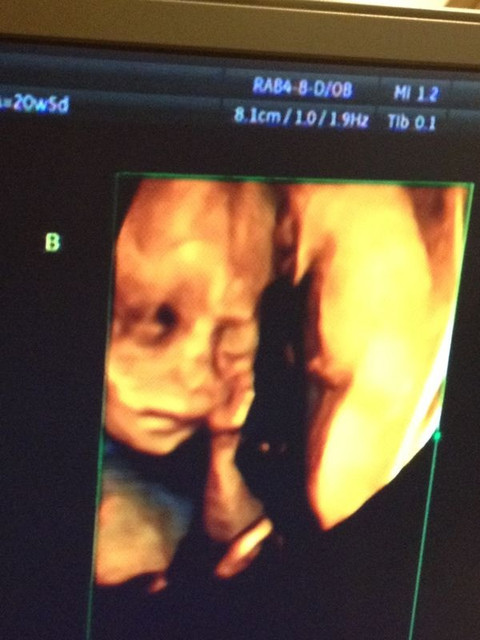

緊接著看B寶寶,B寶寶非常的調皮,動來動去,而且把臍帶繞在兩腿之間,

讓醫生伯伯看了好久,醫生說B寶寶比較難照,因為如果有小雞雞的話,也有可能會被臍帶擋住,

後來醫生震了震我的肚子,讓B寶寶動一動換換位置,結果答案揭曉啦~B寶寶也是女娃喲♥

接著,醫生讓我們看看兩個小寶貝♥

哈哈哈哈~動來動去,一直在吃小手手和揉眼睛真的是可愛極了啦!